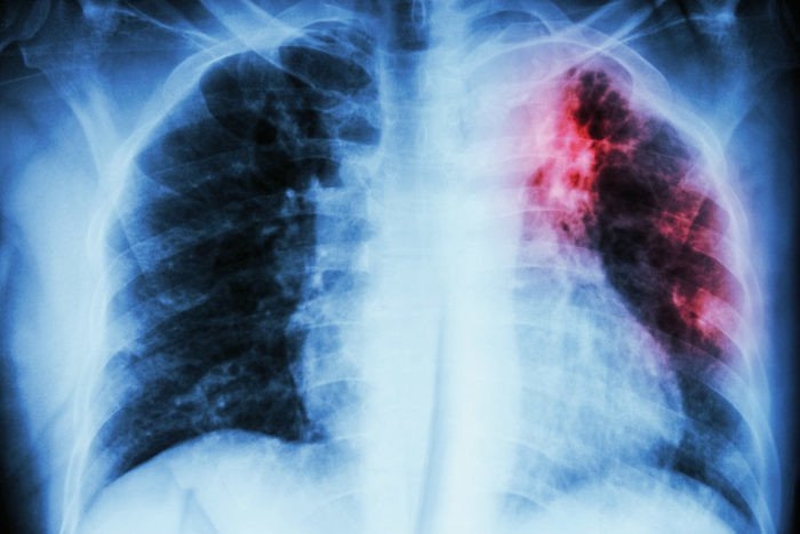

Xơ phổi là tình trạng các mô trong phổi bị tổn thương, trở nên cứng và dày hơn. Sau đó mất dần độ đàn hồi và chuyển hóa thành sẹo trên phổi. Khi bị xơ sẹo ở phổi sẽ gây ảnh hưởng đến việc hít thở của người bệnh. Đây là bệnh không thể chữa lành hoàn toàn mà chỉ điều trị để giảm các triệu chứng của bệnh.

Xơ phổi là bệnh gì? Người bị xơ phổi có lây không? 1 Xơ phổi là bệnh thường gặp ở những người cao tuổi

• Xơ phổi thứ phát: Xuất hiện khi có tổn thương như bị lao phổi, viêm phổi, nhồi máu trong phổi.

• Xơ phổi khu trú: Khi hít phải các chất kích thích như bụi than, silica,...

• Xơ phổi vô căn: Bệnh phổi mô kẽ lan tỏa và bệnh viêm phế nang dị ứng ngoại lai hay còn gọi là bệnh viêm phổi tăng cảm.